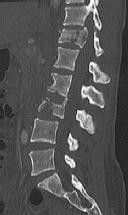

Figure 1 shows a CT from the cervical spine of an 85-year-old woman who fell from a standing height 1 week earlier. She is independent and ambulatory and resides in an assisted living facility. She reports persistent neck pain but denies arm pain or weakness. She is neurologically intact.

Fractures in this region of C2 have a high risk of

Discussion: C

Increased displacement and angulation of odontoid fractures have an increased risk of nonunion. Surgical stabilization has reduced the risks of mortality without increasing the risk of complications compared with nonsurgical treatment options. When treating odontoid fractures, halo vest

immobilization has been shown to increase the risk of dysphagia in the elderly.

The preferred mode of treatment for this patient’s fracture is

4. posterior C1-2 arthrodesis. Discussion: D

Increased displacement and angulation of odontoid fractures have an increased risk of nonunion. Surgical stabilization has reduced the risks of mortality without increasing the risk of complications compared with nonsurgical treatment options. When treating odontoid fractures, halo vest immobilization has been shown to increase the risk of dysphagia in the elderly.

4. Dysphonia Discussion: B

Increased displacement and angulation of odontoid fractures have an increased risk of nonunion. Surgical stabilization has reduced the risks of mortality without increasing the risk of complications compared with nonsurgical treatment